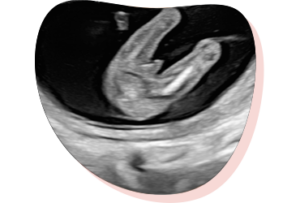

(tussen 7-12 weken)

Na 7 weken zwangerschap kun je een 2D pretecho laten maken. Daarbij krijg je ook het hartje te zien kloppen. Vanaf 12 weken mogen wij het hartje laten horen. Tip: kom met een volle blaas naar de vroege echo voor de beste beelden.